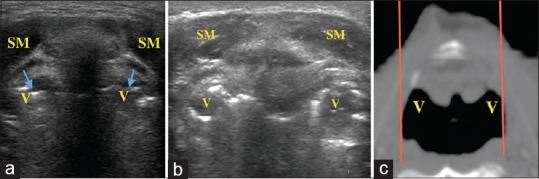

The USG was completed, and checklist successfully followed in all cases. Floor of mouth structures was easy to evaluate and visualized with ease in all the cases. Epiglottis was visualized in 100% cases in transverse plane. Valleculae and pyriform fossae were identified in 82% and 90% of the cases, respectively, and they appeared either as paired air-filled round structures or air-lined linear structures. Complete visualization of vocal cords was seen in 78% females and 63% males. The average time taken to complete the protocol-based study was 10.4 ± 1.4 min.

Application of protocol-based USG for upper airway can allow the examination of structures from tongue to thyroid cartilage in a thorough, convenient, and timely manner. The air filled/lined structures such as valleculae, pyriform fossae, and vocal cords can be visualized in majority of the cases.

所有病例均完成了USG检查,并成功遵循了检查表。口腔底部结构易于评估,在所有病例中均能轻松可视化。会厌在横断面上100%的病例中可见。会厌谷和梨状窝分别在82%和90%的病例中被识别,它们表现为成对的充满气体的圆形结构或气体衬托的线性结构。78%的女性和63%的男性声带完全可视化。完成基于方案的研究的平均时间为10.4±1.4分钟。

应用基于方案的USG对上呼吸道进行检查,可以全面、方便、及时地检查从舌头到甲状软骨的结构。在大多数病例中,可以可视化充满气体/有气体衬托的结构,如会厌谷、梨状窝和声 带。